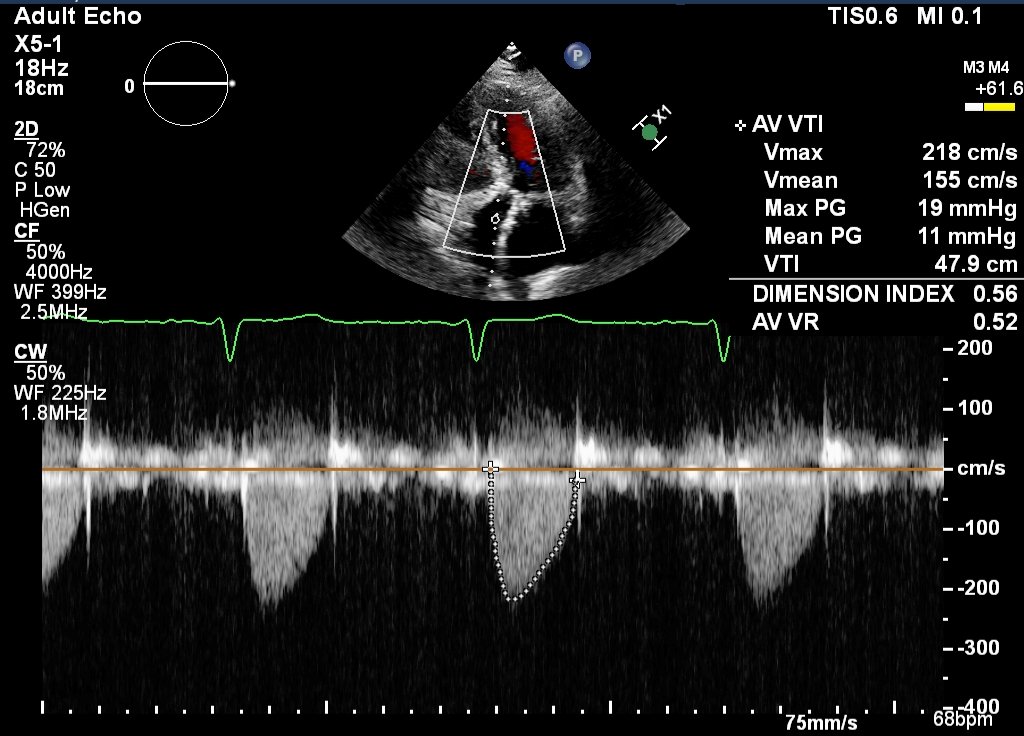

Case 2 - pt in mid 80s, had 23mm tAVR 8yrs prior, again presented acutely in severe HF. Weight <50kg, mildly frail. TTE below...AR was trans, not paravalvular. V-in-V app indicates 23mm TAVI valve would be appropriate.

Again, I suspect most of you will vote for TAVI in someone in their mid 80s...which is what patient had. This patient's post-procedure TTE is below with good outcome.